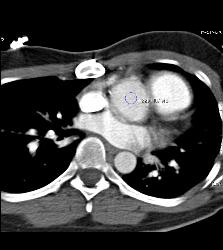

Dilated RCA After Reimplantation S/p Root Repair